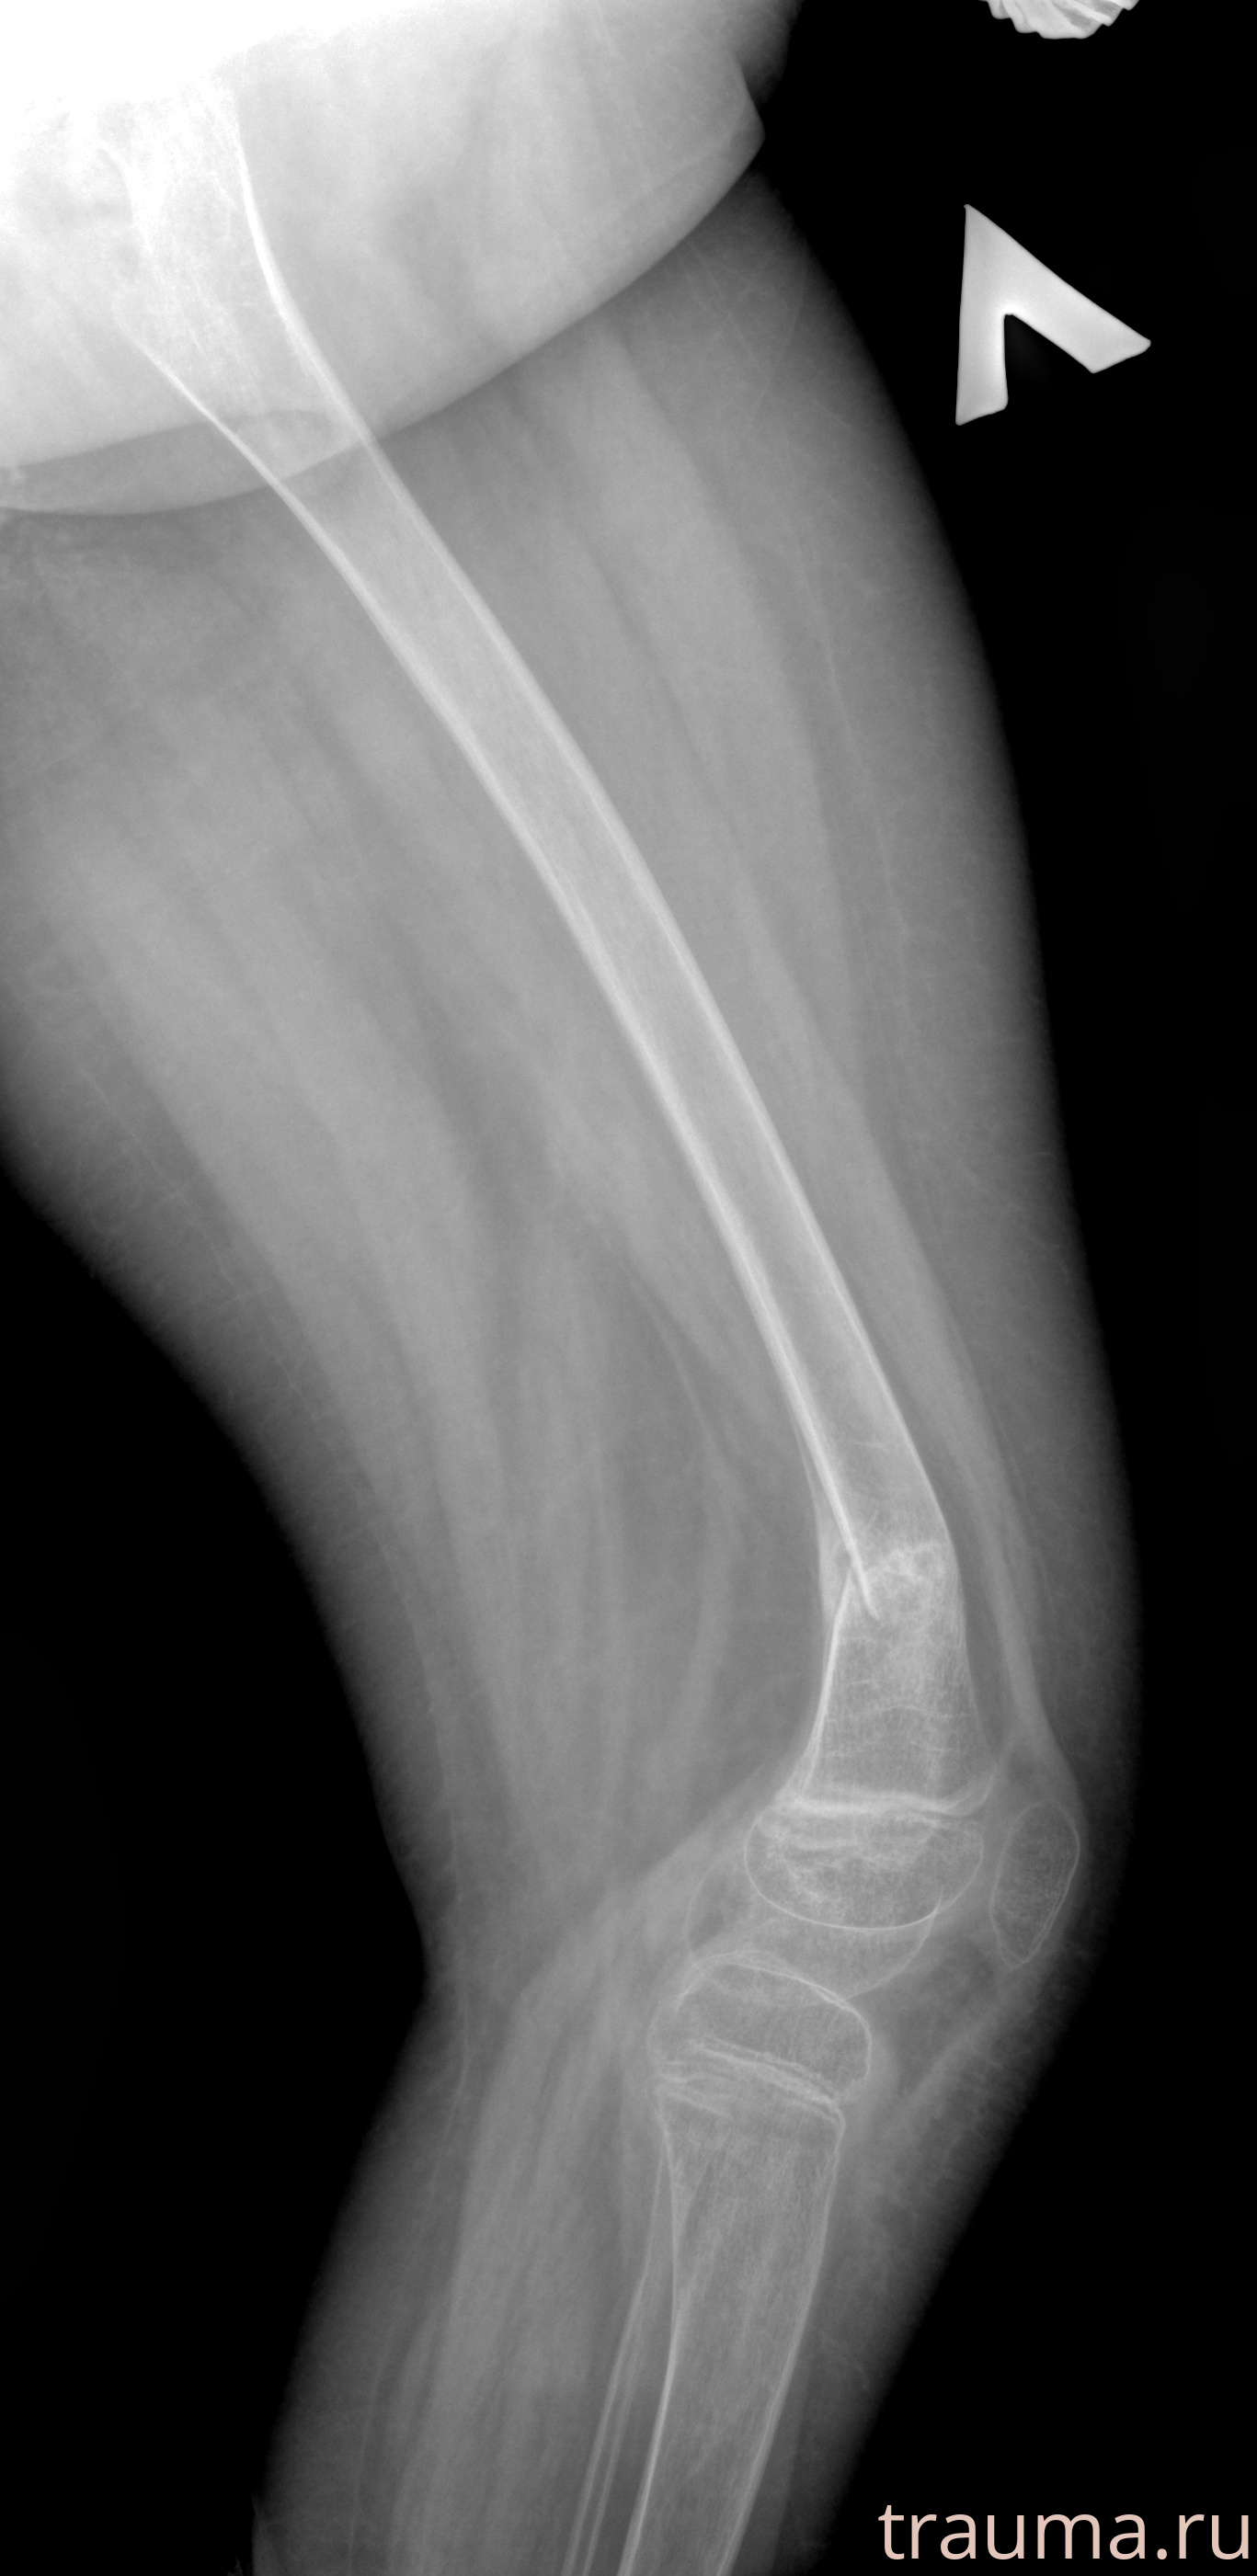

Рентген на дому: по вашему адресу приезжает врач-рентгенолог, травматолог-ортопед с мобильным рентгеновским аппаратом, проводит диагностику травмы или заболевания, делает необходимые рентгенограммы, дает рекомендации по дальнейшему лечению. Получить качественные снимки в домашних условиях возможно благодаря уникальной методике, разработанной МосРентген Центром для института  Склифосовского